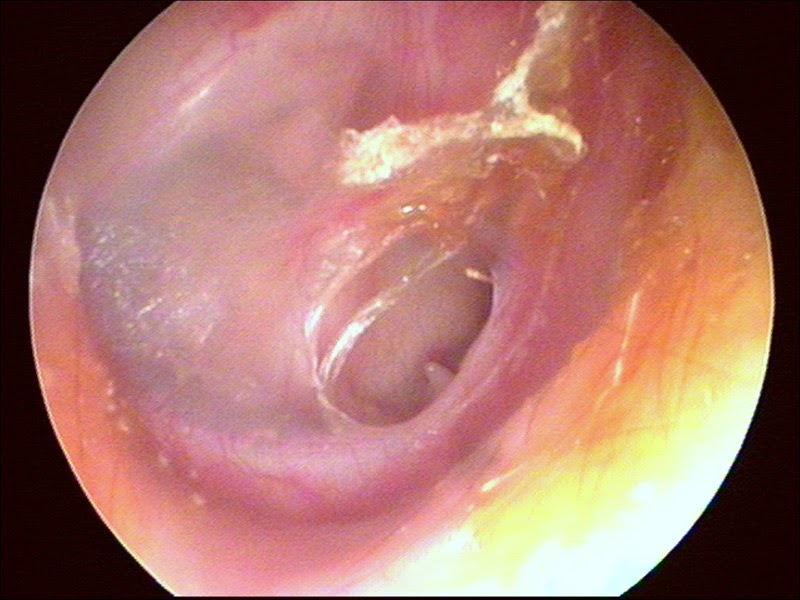

| figura 1 : otoscopia OMC |

| FIGURA 2 : Otoscopia OMC |